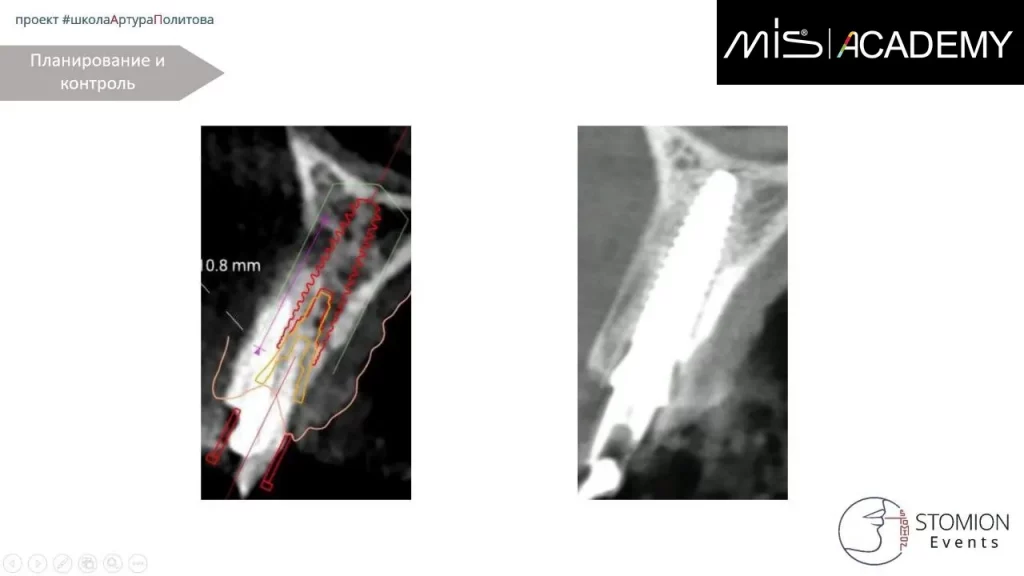

Удаление 1.2, тип лунки II

— По НХШ установлен имплантат MIS C1 3,3х13 (для получения торка)

— Забор аутокости с бугра ВЧ, IDR, СТТ вестибулярно

— Коннект 3мм